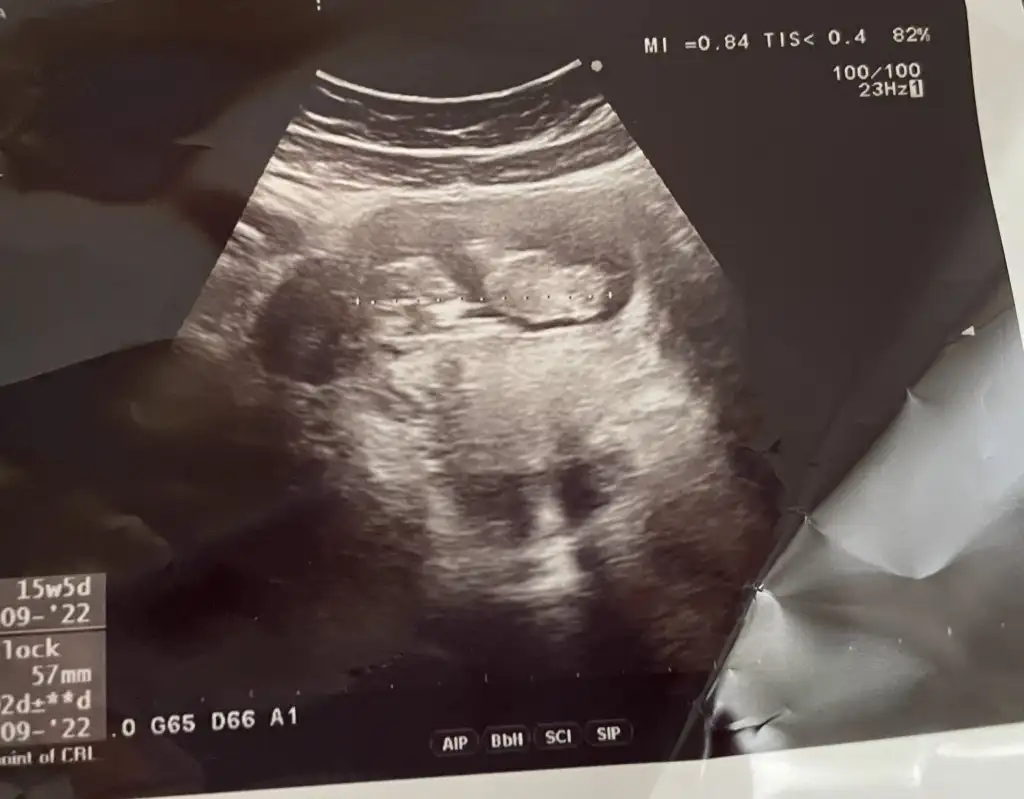

Hadi hayırlısı sağlıkla gelsin de .16.haftada söyleyecek doktor. Size de yazarım

tahmin için biraz büyük15 şuan, görüntüler 13 haftalıktan göstermedi bebiş o gün :)

Teşekkür ederim hayırlısı inşallahtahmin için biraz büyükama iki ve üçüncü foto çok net kız canım